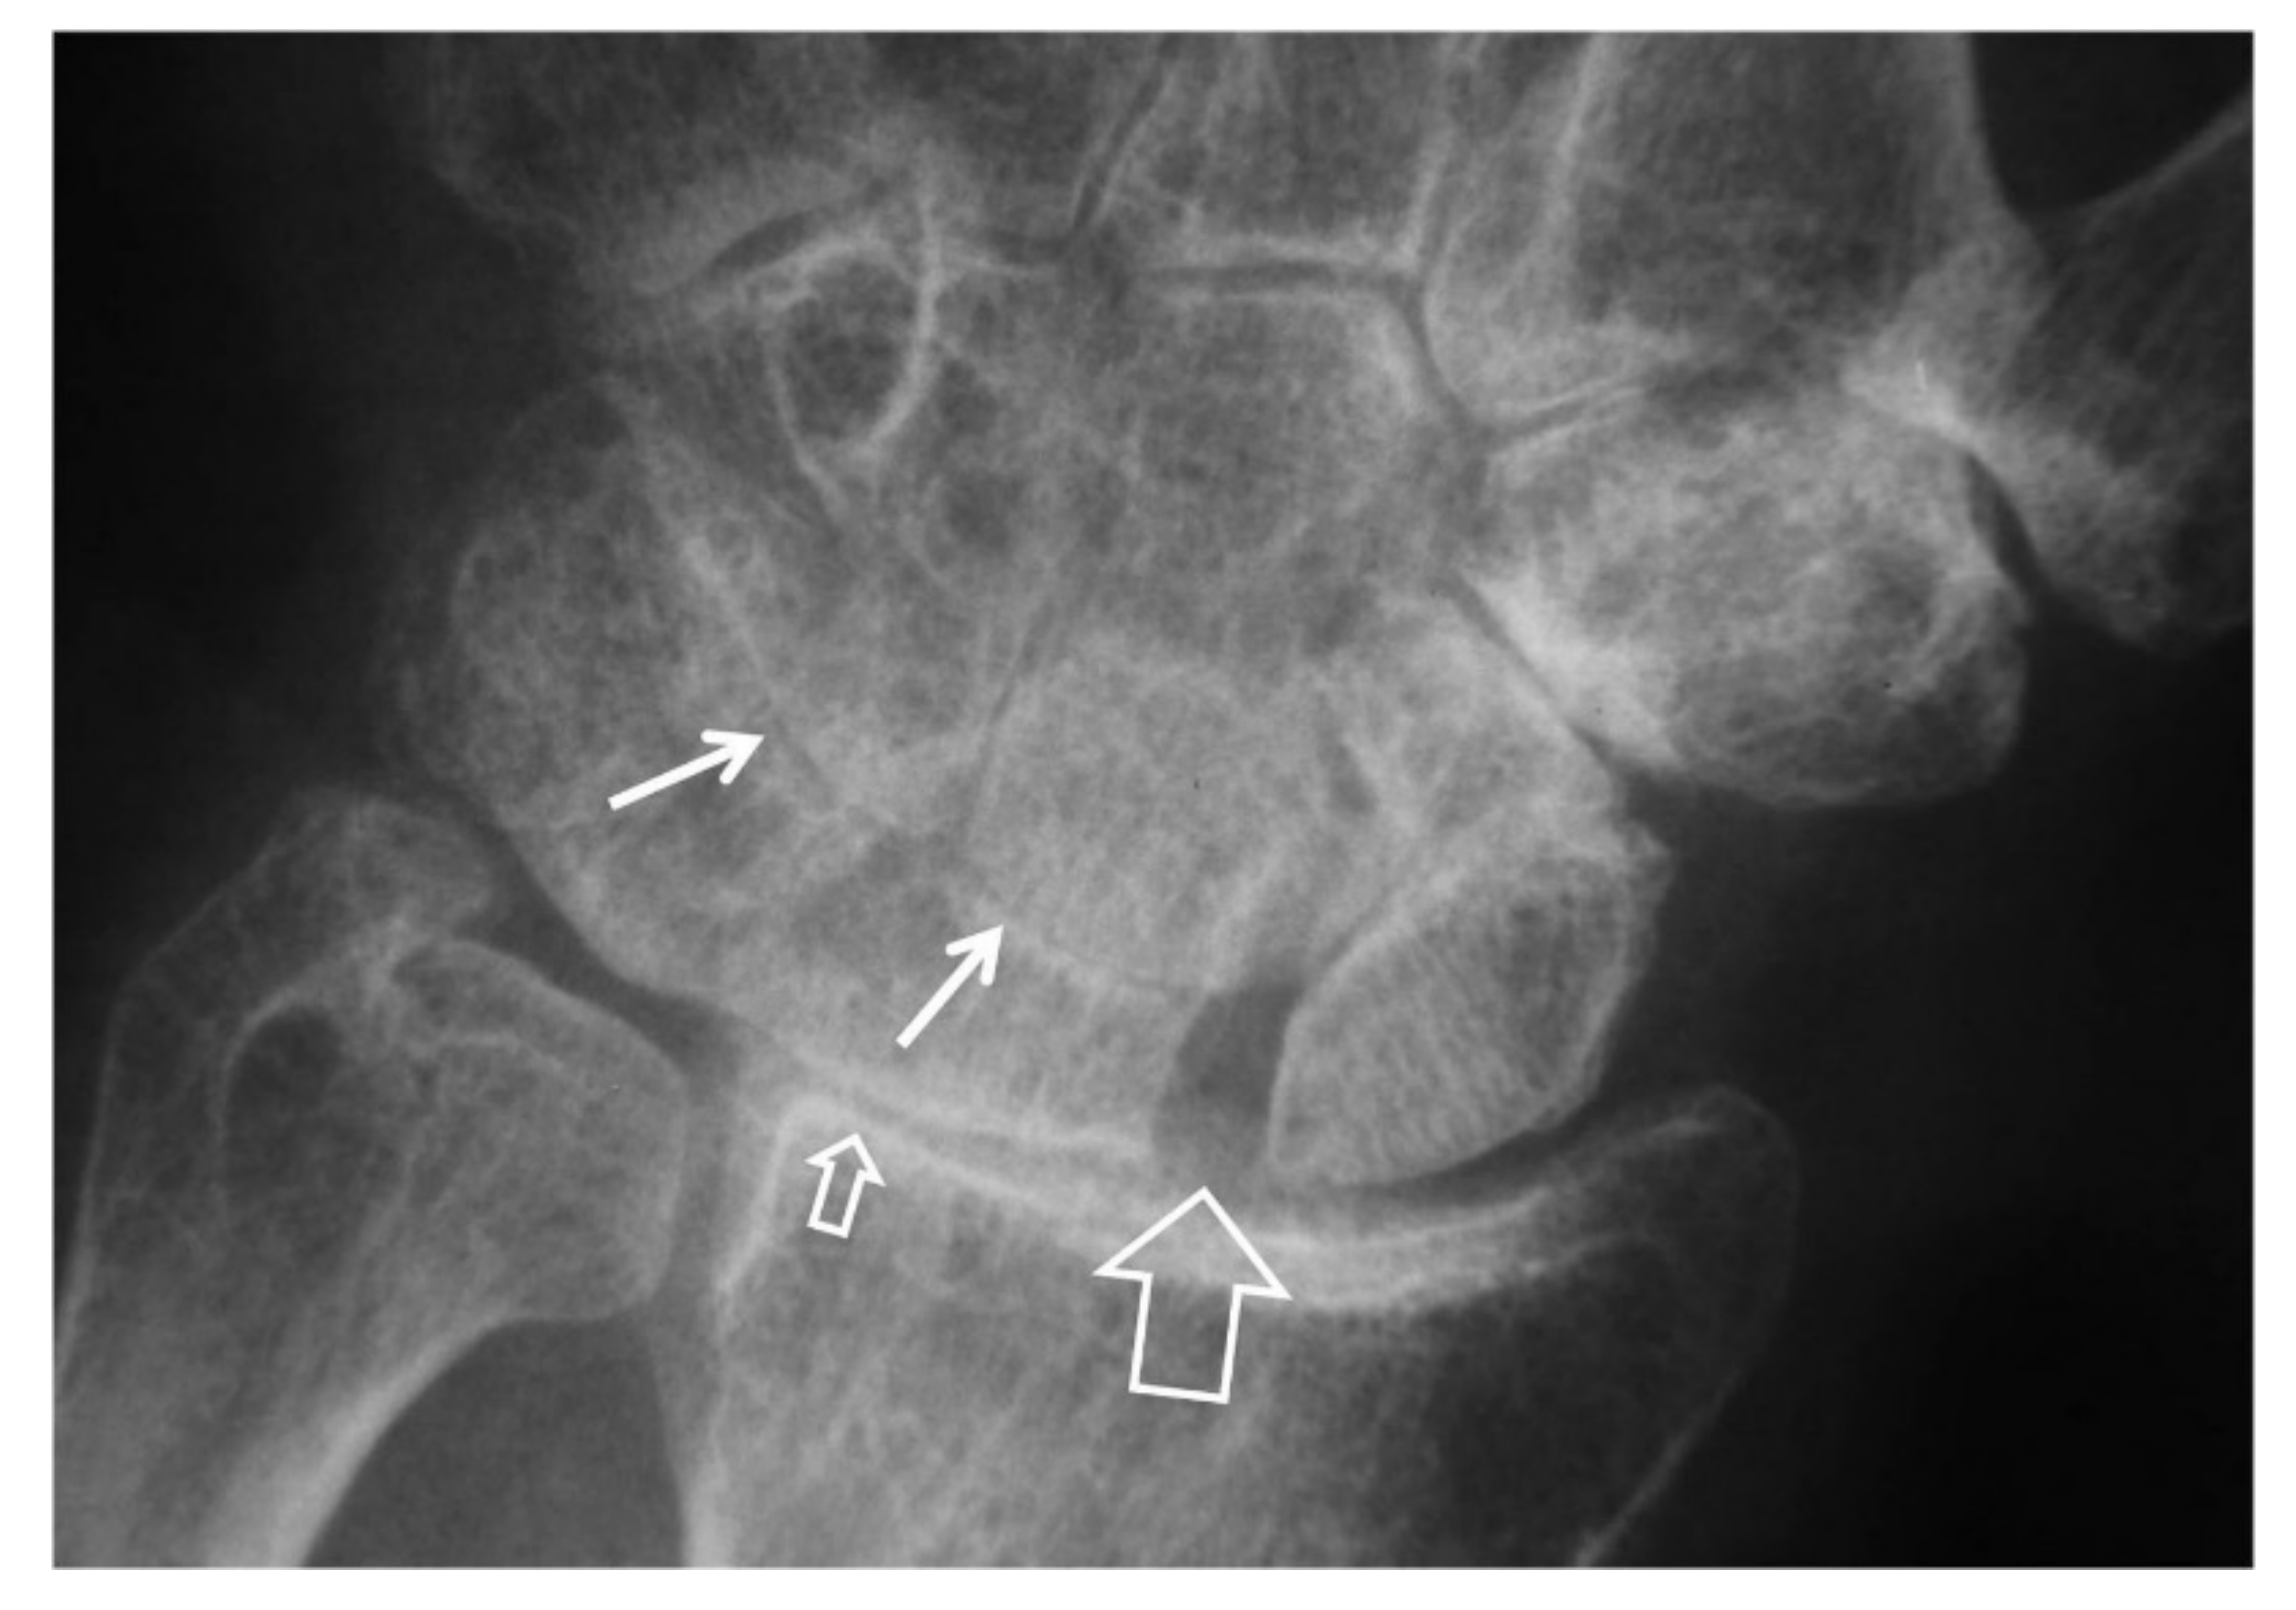

Figure 4.

A 55-year-old male patient with long standing wrist pain and limited range of motion. Scapholunate ligament disruption (large open arrow), radiolunate joint space narrowing (small open arrow) and mid-carpal osteoarthritis (arrows) are diagnostic of a SLAC wrist. The altered shape of the scaphoid is due to its rotatory subluxation.